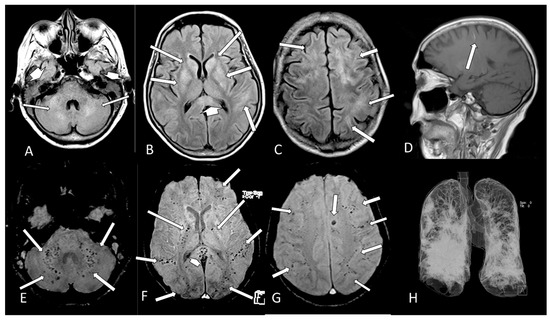

| 15 | M | 26 | seizure, hemiparesis | no | no | no | no | temporo-occipital hypersignal on FLAIR, hemosiderosis (MRI) | >50% | ICU | no | |

| 16 | F | 34 | yes | headache | yes | yes | no | no | olfactory bulb injury (MRI) | <25% | internal | no |

| 17 | F | 43 | no | headache, dizziness | no | yes | yes | no | olfactory bulb injury (MRI) | - | internal | no |

| 18 | M | 40 | yes | headache, hemiparesthesia, visual field fog | yes | yes | no | no | corpus callosum restricted DWI lesion and olfactory bulb injuries (MRI) | - | internal | no |

| 19 | F | 35 | yes | headache | yes | yes | no | no | olfactory bulb injury (MRI) | normal | internal | no |

| 22 | M | 62 | - | severe depression, parkinsonism, coma | yes | no | yes | ventilator | olfactory bulb injury (MRI) | >50% | ICU | no |

| 24 | F | 25 | yes | headache | yes | no | no | no | olfactory bulb injury (MRI) | normal | external | no |

| 25 | F | 36 | - | headache | - | - | - | no | olfactory bulb injury (MRI) | normal | external | no |

| 27 | F | 61 | - | headache | - | - | - | no | cortical/subcortical hematomas and pale globes microbleedings + olfactory bulb injury (MRI) | >50% | internal | no |

| 28 | M | 80 | - | seizure, recurrent syncope | yes | yes | yes | O2 catheter | frontal microbleeding and olfactory bulb injury (MRI) | <25% | ICU | no |

| 30 | F | 70 | - | yes | yes | yes | ventilator | microbleedings in base ganglia, brainstem and cerebellum (MRI) | >50% | ICU | yes | |

| 31 | M | 62 | - | coma | yes | yes | yes | ventilator | cerebellum, corpus callosum and parietal white matterbleeding and restricted DWI small lesions (MRI) | >50% | ICU | no |